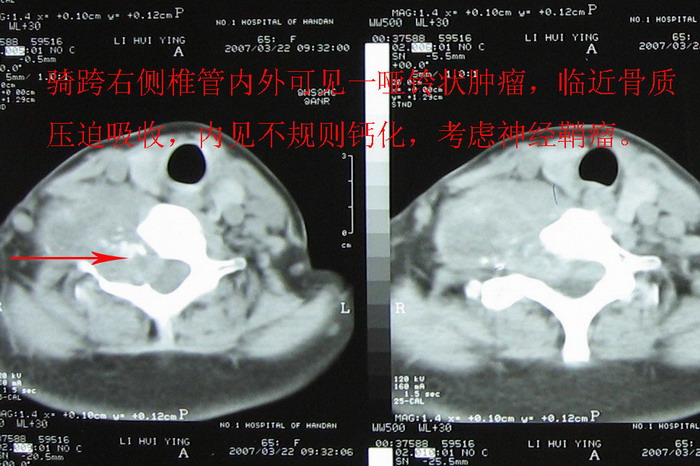

支持考虑:神经原性肿瘤。(右侧椎间孔扩大,椎板破坏,局部明显的软组织肿块,并与椎管 神经根关系密切。)

支持考虑:神经源性肿瘤(右侧椎间孔扩大,椎板破坏,局部明显的软组织肿块,并与椎管神经根关系密切)。